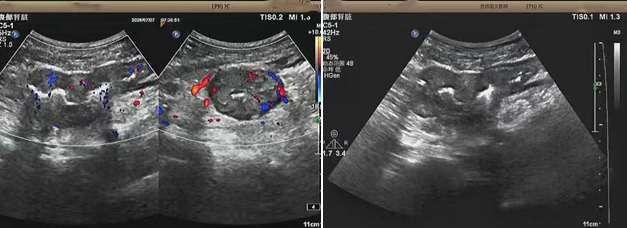

超聲檢查的結果進一步揭示了病情的細節(jié):下腹部偏左腸壁顯著增厚,原本清晰的層次結構遭到破壞,周圍脂肪間隙變得模糊,網膜回聲也出現(xiàn)增強的現(xiàn)象,同時,腸腔狹窄的情況也得到了確認。經過完善的檢查,最終將病變精準定位在乙狀結腸 - 直腸交界區(qū),并且對病變范圍及周圍浸潤情況做出了評估,這些關鍵信息為后續(xù)的診療工作提供了重要依據(jù),讓醫(yī)生們能更有針對性地制定治療方案。

我院超聲檢查在此次診療過程中展現(xiàn)出了顯著的技術亮點。一方面,它能做到 “明察秋毫”,通過高頻探頭可以清晰地顯示腸壁各層結構的變化,為臨床判斷病變性質提供了客觀、準確的依據(jù),讓醫(yī)生能更清晰地了解腸道內部的病變狀態(tài)。另一方面,它實現(xiàn)了 “精準評估”,不僅準確找到了病變的位置,還能全面評估病變對周圍組織的影響,這對于協(xié)助醫(yī)生制定科學合理的治療方案起到了至關重要的作用,有助于提高治療的有效性和安全性。